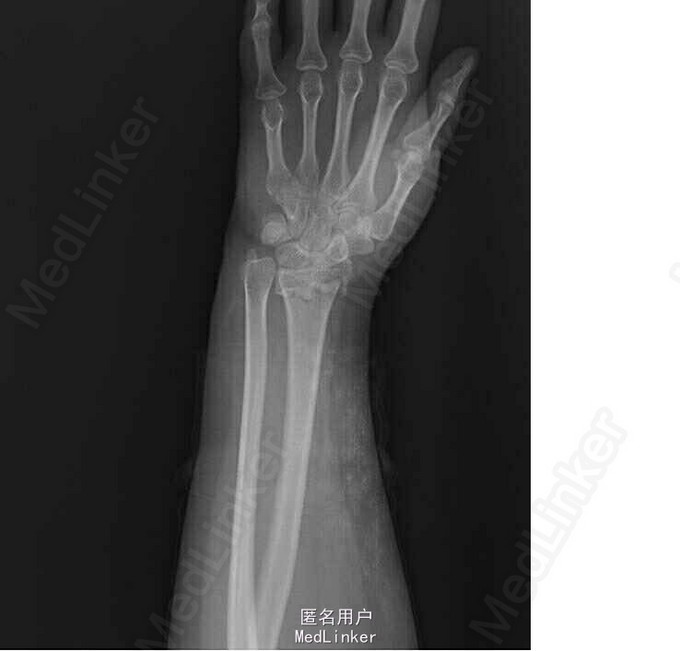

患者2小时前外伤后摔倒在地,出现左侧腕关节疼痛伴活动受限,双手掌心擦伤,左手腕部尺侧擦伤。于急诊行左手正斜位示:左侧桡骨远端骨折(barton骨折)。急诊予石膏托固定腕关节,为行手术治疗,急诊收入院

左手腕关节压痛明显,未触及骨折断端,局部软组织挫伤,肿胀明显,左手手指活动可,感觉无明显异常。 左手正斜位示:左侧桡骨远端骨折(barton骨折)

诊断:右侧桡骨远端骨折(barton骨折) 双手皮肤软组织挫伤 行左桡骨远端骨折切开复位内固定术